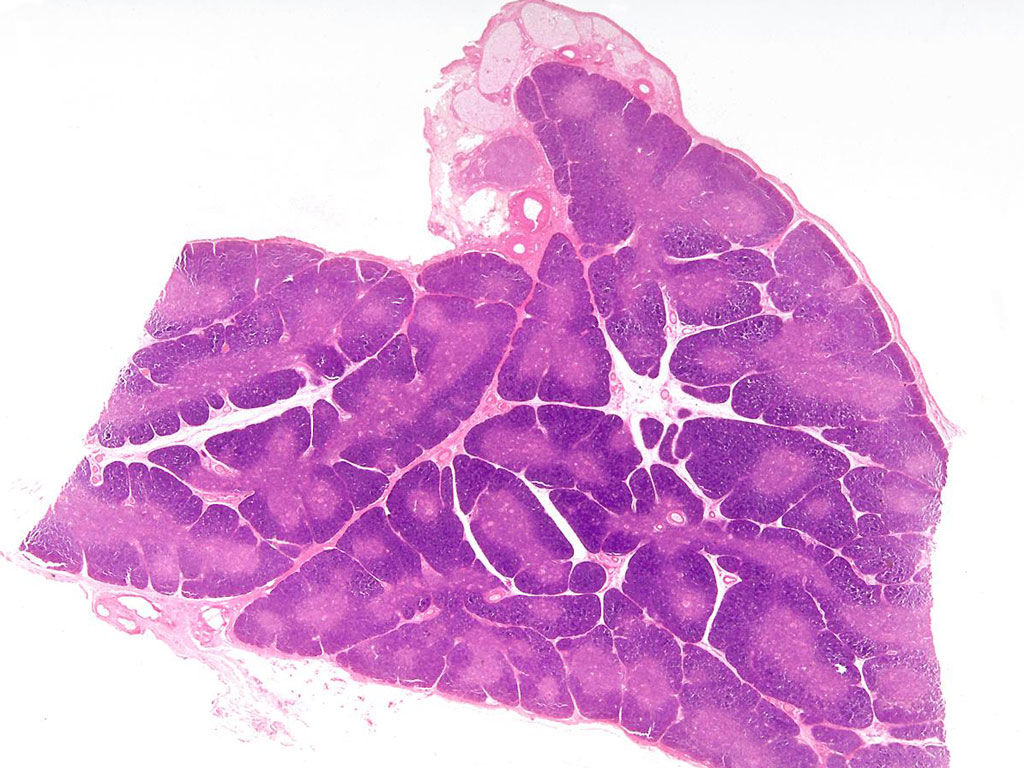

Question 2

Question

Indiquer dans quel organe on se trouve (en h à g), l'unité structurelle de cet organe (en h à d) ainsi que les structures pointées.

Image:

Thymus (image/jpeg)

Answer

thymus

lobule thymique

médulla

cortex